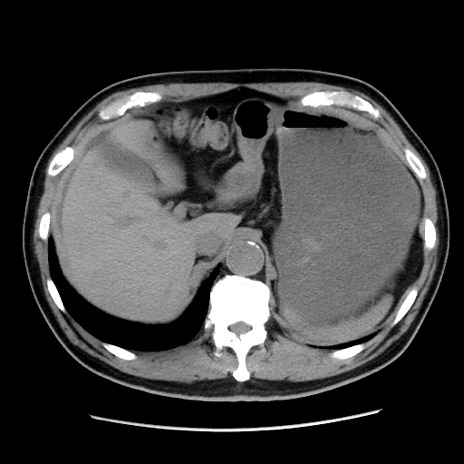

症例16(横断像)

【症例】 70歳代男性

【主訴】 腹痛、嘔吐

【現病歴】 約1ヶ月前より間欠的に腹痛と嘔吐あり、当院消化器内科を受診したところCTで多発する肝臓のLDAを指摘され、精査中であった。以降は消化器症状は安定していたが、2日前より嘔気と腹痛があり、同日より排便・排ガスが消失した。改善認めず、 本日、救急外来を受診した。

【既往歴】 大腸ポリープ切除後。

【身体所見】意識清明・会話良好、BT 36.3℃、BP 127/80mmHg、 P 80bpm、腹部:膨満あり、平坦・軟、上腹部正中および下腹部正中に圧痛あり、反跳痛なし、筋性防御なし。

【データ】WBC 7200、CRP 0.77